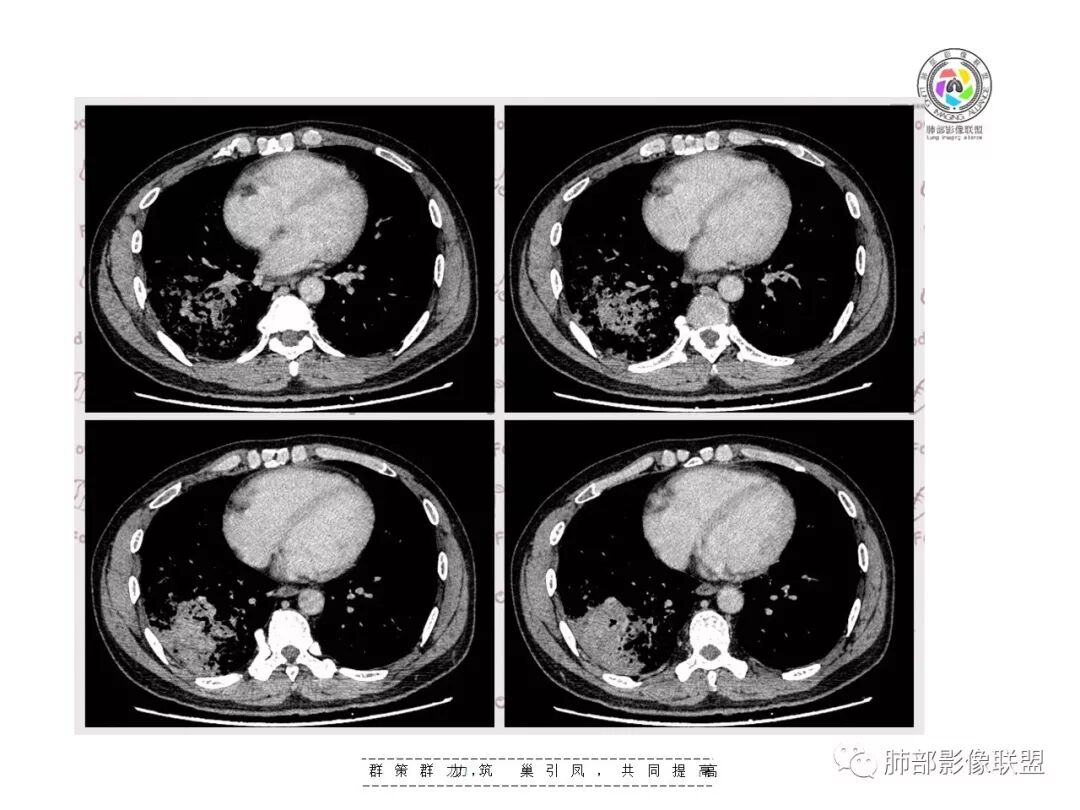

【影像资料】

王秀仙东宁市第二人民医院影像科:晨读:右肺下叶实变及磨玻璃影,边缘有收缩有膨隆,部分支气管进入扭曲扩张,磨玻璃影边缘清晰,实变影明显强化,内可见血管造影征,纵膈及肺门淋巴结肿大并强化,考虑粘液腺癌。

登封市三康医院(刘权威):右下肺肺不张,磨玻璃影,边缘清楚,空气支气管征,增强有强化,纵膈及右肺门淋巴结肿大并强化,考虑恶性肿瘤,粘液腺癌可能。

下叶外基底段为主实变,周围GGO

这个病灶很有特色

分布:沿支气管段、亚段朝外蔓延分布

实变+GOG

实变区边缘收缩,支气管走形自然

但是我们也可以看到实变区很多地方没看到支气管,也就是支气管在实变区分布不均匀,提示有些地方支气管腔内有物质填塞,显示不清

GGO边界大部分不清楚,内有树芽征,中央间质均匀增厚

实变区边界清、凹陷及平直,内部密度均匀,强化均匀,支气管在密实处填塞,其余部分通畅、走形自然,中央间质均匀增厚